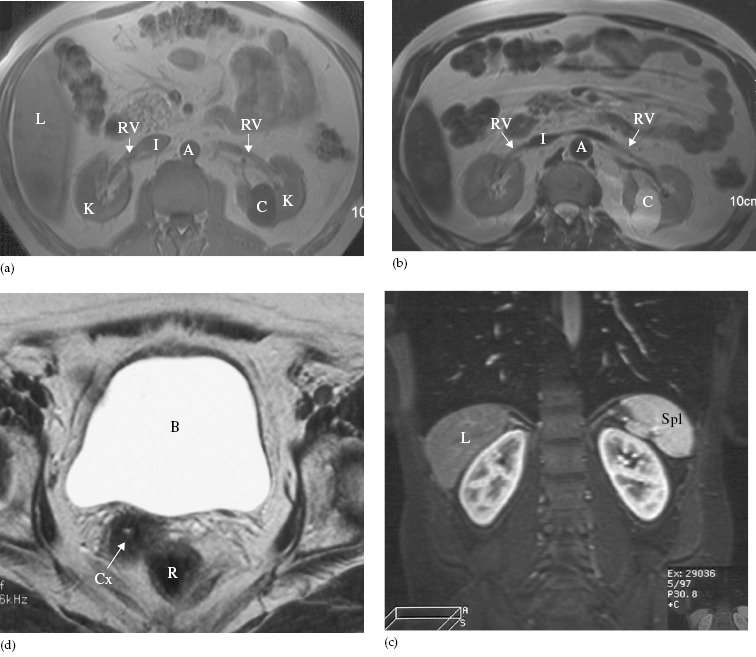

X-ray images of the kidney, ureter, and bladder. (A) Pretreatment …

Urinary Tract | Radiology Key

Urinary System | Radiology Key

Urinary System | Radiology Key